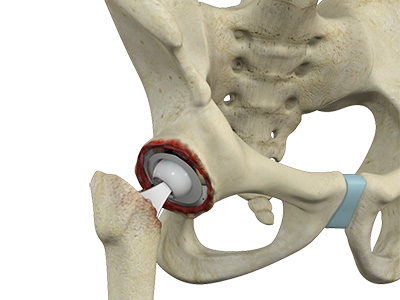

Robotic Assisted Hip Replacement Total Hip Replacement

Total Hip Replacement Outpatient Hip Replacement

Rapid Recovery Hip Replacement Minimally Invasive Total Hip Replacement

Minimally Invasive Total Hip Replacement Complex Primary Hip Replacement